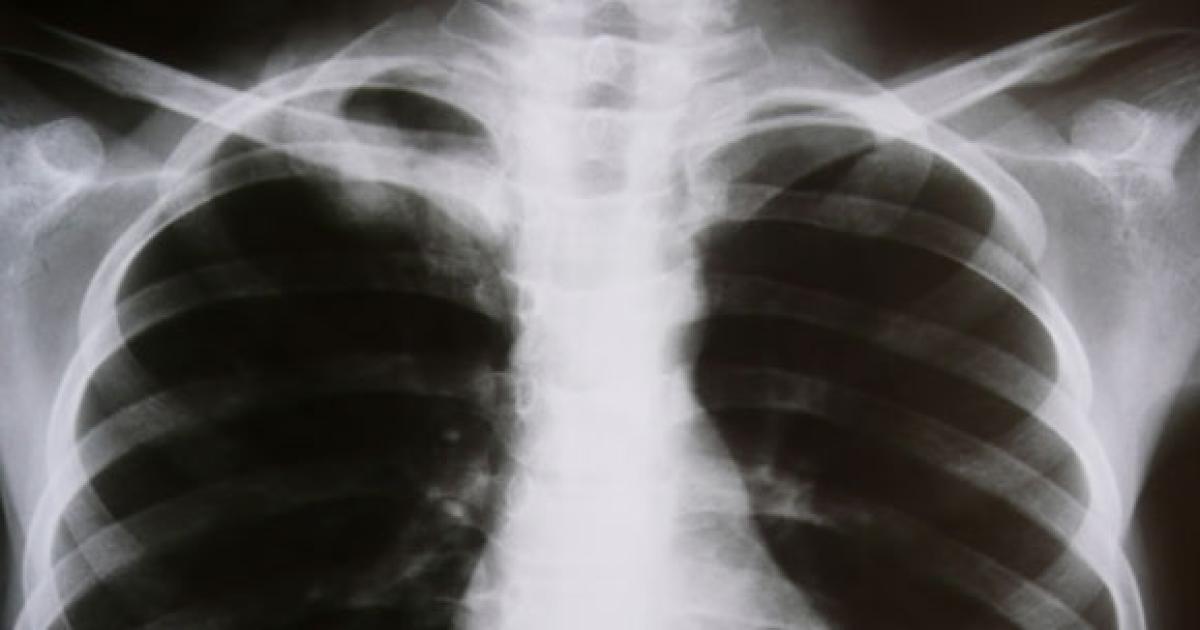

These were cancers where other factors came into play. An example of this is lung cancer, which is linked to smoking. The scientists, in fact, make this point when they say that a heavy smoker not ending up with cancer is plain ‘good luck’ because the chances that he will are actually high.